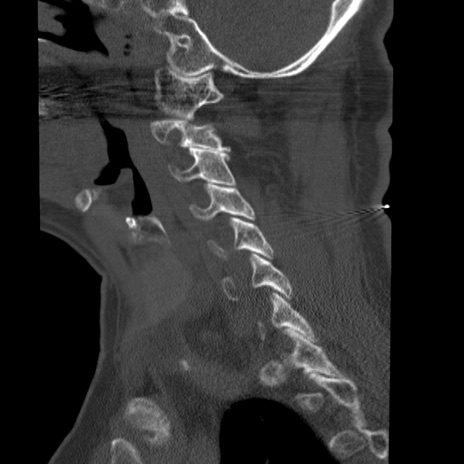

症例50 頚椎CT(矢状断像)

頚椎CT

横断像